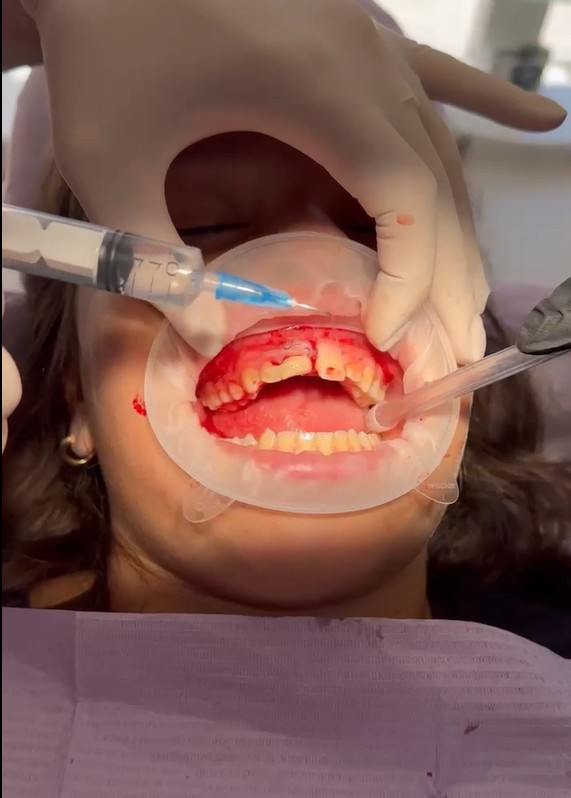

2. Suturimi i indeve të buta

Për të krijuar një mbyllje të sigurt të plagës dhe për të stabilizuar strukturat e dëmtuara, u krye suturimi i indeve të buta. Ky hap ishte thelbësor për të parandaluar infeksionin, për të ruajtur stabilitetin e zonës dhe për të lehtësuar procesin e shërimit.

3. Splintimi stabilizues – kombinim i kompozitit dhe telit ortodontik

U përdor një teknikë e kombinuar splintimi:

• Kompozit në anën vestibulare, i cili jep fleksibilitet dhe estetikë.

• Tel ortodontik në anën palatinale, i cili përforcon stabilitetin pa e ngurtësuar dhëmbin në mënyrë të tepruar.

Ky lloj splintimi i “butë” (flexible splint) është i rekomanduar në trauma të këtij lloji, sepse ndihmon në rigjenerimin e ligamentit periodontal.